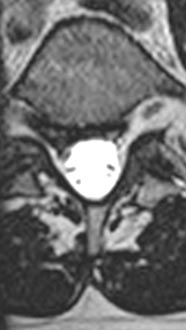

44 year old man with severe low back pain with intermittent radiation of the pain down the right leg. After undergoing conservative treatment, continued to have debilitating pain. MRI revealed a right paracentral disc herniation but CT scan revealed a unilateral pars fracture. After debating on microdiscectomy vs fusion, patient elected to undergo lumbar fusion. 4 months postop patient returned to surfing again. 9 months postop patient wrote “My recovery continues to do very well and we just got back from 8 days camping which including mountain biking, hiking, and a lot of work. Surfing almost every day and life is good…you have helped get my life and my families life back to normal.”